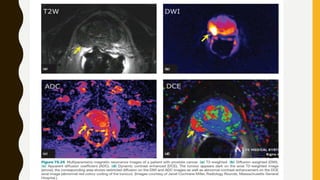

Diffusion-Weighted Imaging/Apparent Diffusion Coefficient

• DWI assesses the diffusion of water (Brownian motion) within the magnetic field. The

MR magnet is able to detect the phase shift changes in the motion of the water

protons. The more cellular a tissue is, the closer the cells are together, resulting in a

limited motion of water, which is reflected as a high signal on DWI (Manenti et al,

2006).

• As with all MR sequences, there are several details that one should observe. Most

important is the b-values associated with DWI. B-values represent a threshold for

detecting restriction. As a b-value is increased, less restricted tissues do not exhibit a

high signal on DWI.

• DWI can include multiple b-values, and it is recommended to include at least one b-

value greater than 1000 (Rosenkrantz et al, 2010). The ADC is a quantitative

assessment of the DWI. This is represented by an area of low signal on the images

(dark spot) (Fig. 2-30D). Some authors recommend including a b-2000 sequence on

DWI; it has been shown that prostate cancer exhibits a high SI compared with the rest

of the gland (Ueno et al, 2013) (Fig. 2- 30F).

• The ADC value computed from DWI has been shown to directly correlate with

score (Turkbey et al, 2011). Intuitively this makes sense because an increase in

Dynamic Contrast Enhanced Magnetic Resonance Imaging

• DCE-MRI refers to T1-weighted imaging with Gd-based contrast agents. DCE-MRI is

not a simple assessment of enhancement versus no enhancement. It assesses

permeability and perfusion of the prostate by obtaining multiple image acquisitions

over 5 to 10 minutes at a temporal resolution of less than or equal to 5 seconds

(Verma et al, 2012). The 5-second temporal resolution requires a decrease in the size

of the imaging matrix, therefore resulting in a lower resolution image. DCE- MRI is

meant to obtain clear anatomic images; it is used to assess the blood flow and

permeability throughout the gland over time. DCE-MRI provides qualitative,

semiquantitative, and quantitative information regarding enhancement within the

prostate.

• A qualitative approach consists of visually assessing early enhancement and early

washout within the prostate. The use of computer aided diagnostic systems allows

one to obtain specific information with regard to enhancement characteristics. A

semiquantitative approach assesses enhancement over time (Tofts et al, 1991). There

are three distinct curves associated with prostate imaging (Fig. 2-31). Because of the

overlap of all three curve types with benign conditions, it is useful to combine these

approaches in a MP-MRI